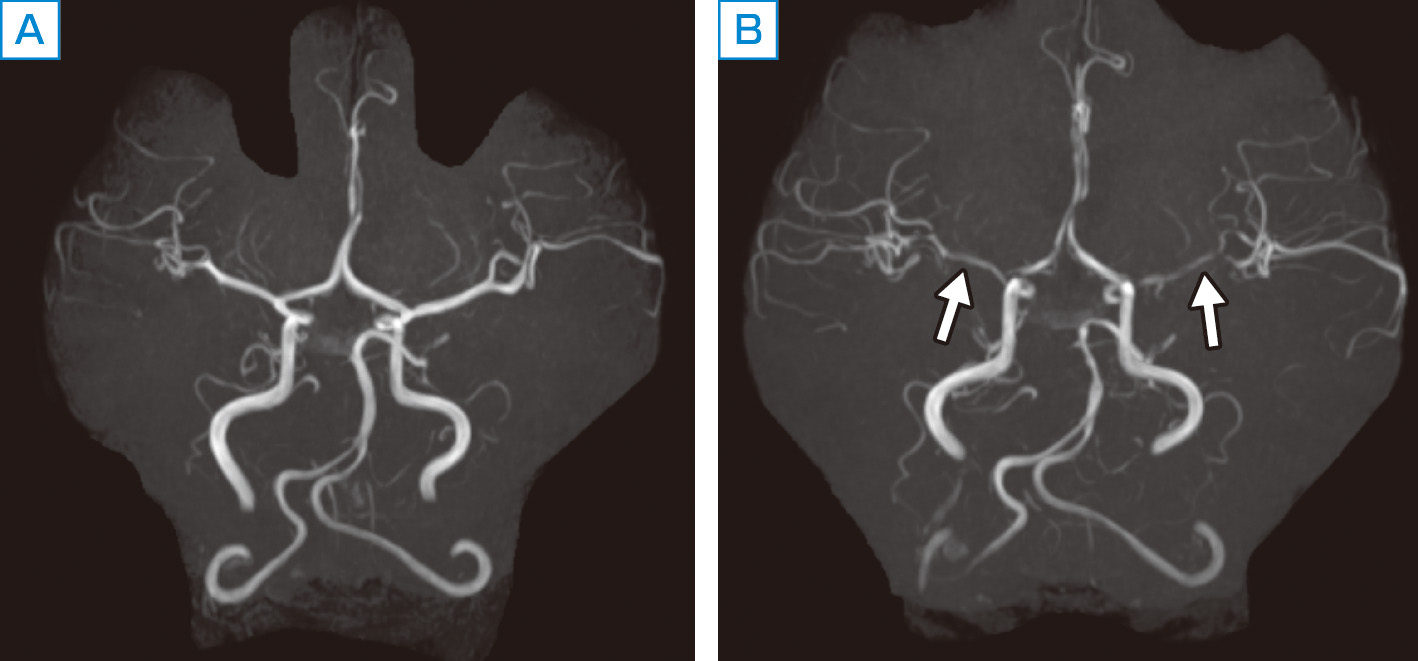

経橈骨動脈脳血管内治療(TRN)超入門:145本のWEB動画と。経橈骨動脈脳血管内治療(TRN)超入門:145本のWEB動画と。商品詳細ページ | メディカルブックセンター。茨城県筑西市産コシヒカリ10kg(令和6年度)5分つき。脳血管内手術 | 患者さまへ - 鳥取大学医学部 脳神経医科学講座。血管内治療 - 診療案内 - 愛知医科大学医学部 脳神経外科。鳥取大学医学部 器官制御外科学講座 心臓血管外科学分野 TOTTORI。血管内治療 - 診療案内 - 愛知医科大学医学部 脳神経外科。朝倉書店『内科学』(第12版)デジタル付録。超音波および神経刺激の小児アトラス-ガイド付き局所麻酔-第27章。。経橈骨動脈脳血管内治療(TRN)超入門:145本のWEB動画とイラストで学ぶ 難易度別テクニック&エッセンス\r\r購入後一読のみ。メジカルビュー社|脳神経外科|新NS NOW 11 Advanced脳血管内治療。\r書き込み、線引き、裁断なし。脳動静脈奇形に対する血管内治療 | 脳血管内治療学研究センター。\r目立った折れや汚れもなく美品だと思います。脳神経血管内治療科。